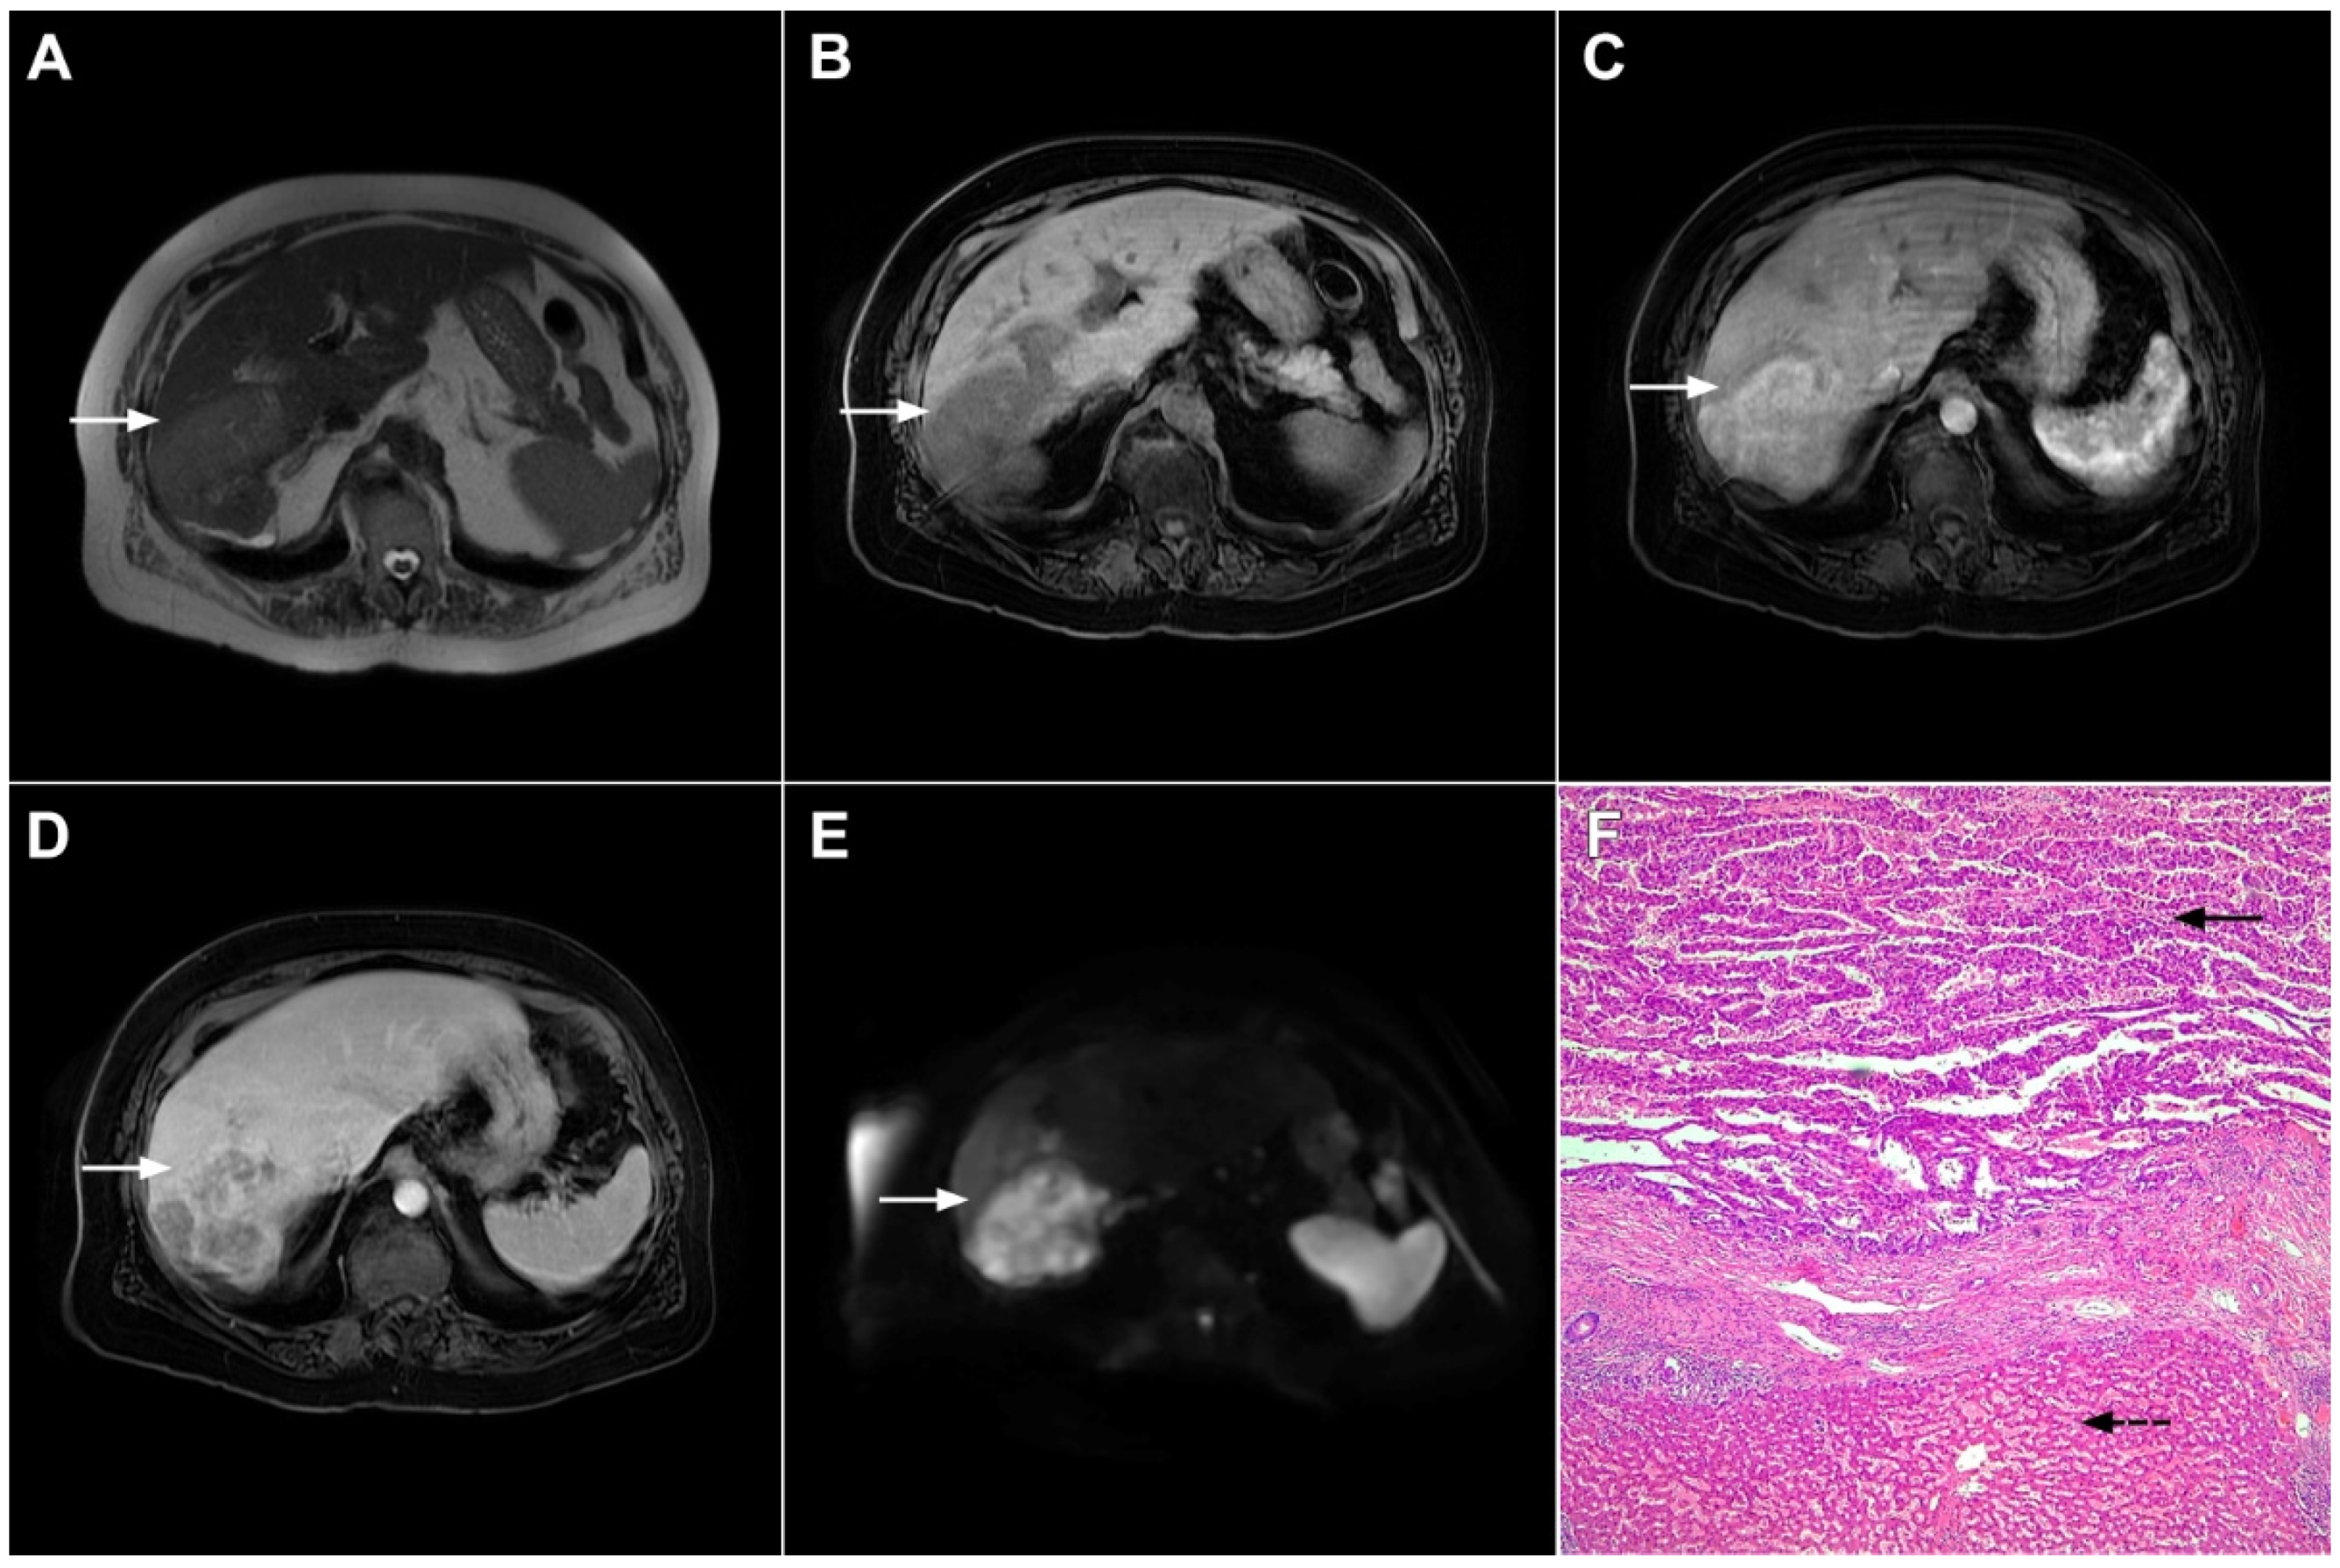

Figure 1.

Typical intrahepatic mass-forming cholangiocarcinoma in 68-year-old woman. On axial T2-weighted image a lobular heterogeneously hyperintense tumor (arrow) is seen, located centrally in the liver segment IVB (A). The lesion (arrow) is hypointense in a plain T1-weighted image (B) with irregular ring enhancements in the arterial phase (C) and progressive enhancement in the portalvenous (D) and delayed phase (E). Note the perilesional biliary dilatation. Hematoxylin and eosin (H&E) staining (F) showed cholangiocarcinoma (arrow) and normal liver parenchyma next to the tumor (dashed arrow); original magnification ×40.